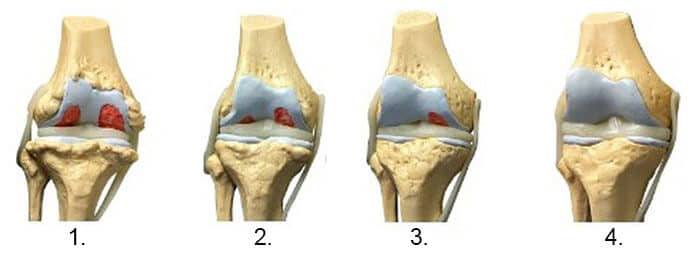

1. Nedostatak hranjivih tvari u zglobu. Hrskavično tkivo je uništeno.

2. Obnova hrskavičnog tkiva u zglobu nakon 2 sedmice upotrebe gele Bone Control.

3. Obnova hrskavičnog tkiva zgloba nakon 3 sedmice upotrebe gele Bone Control.

4. Zdrav zglob nakon jednog kursa gele Bone Control.

- Snimak ispod pokazuje tipičnu sliku oporavka zgloba koljena.